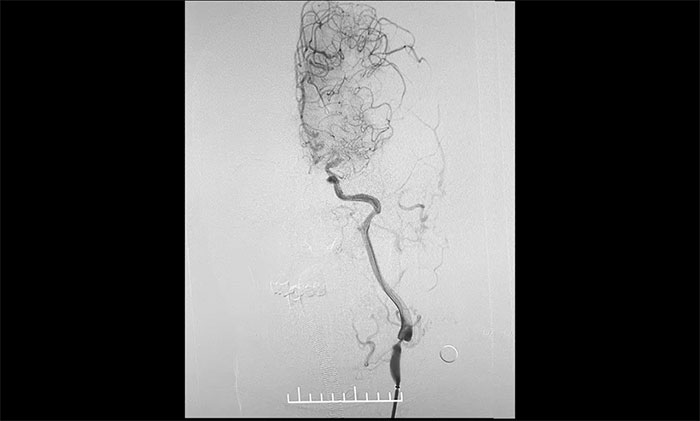

术中,席刚明教授、王贵平博士先对左颈内动脉起始段重度狭窄处进行开通治疗,在保护伞下经过多次球囊扩张后,顺利释放支架于左颈内动脉起始段至左颈总动脉末段,造影见狭窄明显改善,顺利开通血管。

术中,席刚明教授、王贵平博士克服血管迂曲困难,经过多次尝试,多次球囊扩张、“按摩”后,最终顺利释放密网支架至左颈内动脉眼动脉段、左颈内动脉床突段、左颈内动脉海绵窦段。造影及3D造影见,动脉瘤瘤内造影剂明显滞留,左颈内动脉、左大脑前动脉显影可,载瘤动脉通畅,获得了理想的血管重建。复查造影,左颈总动脉造影见左颈总动脉、左颈内动脉、左大脑前动脉显影可。CT见支架打开贴壁满意,XperCT未见颅内出血,手术圆满完成,顺利拆除“不定时炸弹”并打通大脑生命线。

▲ 颈动脉重度狭窄解除,打通大脑生命线

▲ 顺利拆除“不定时炸弹”